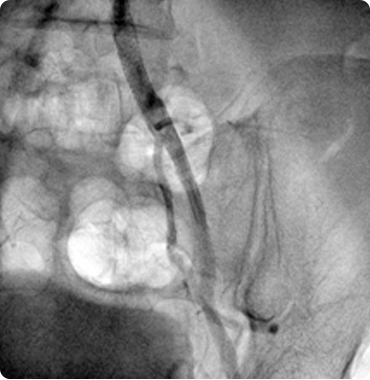

Together with a team of trained staff, his goal is to provide top care so that patients can achieve and maintain a healthy heart. He has done hundreds of angiographies and angioplasties...